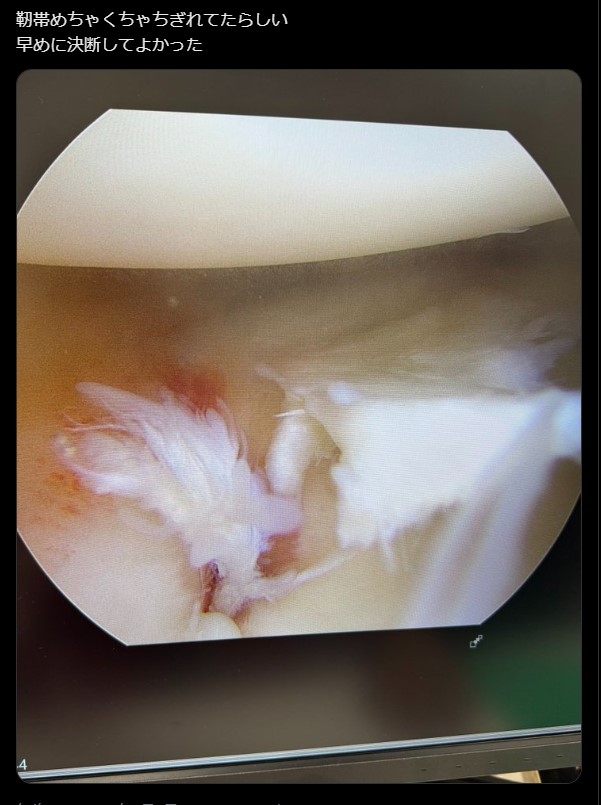

これは痛そう!平本のちぎれた靭帯(@renhiramotoXXより)